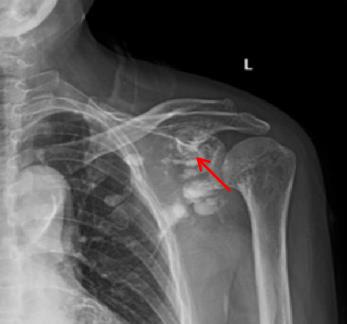

No.7

X线

2

1